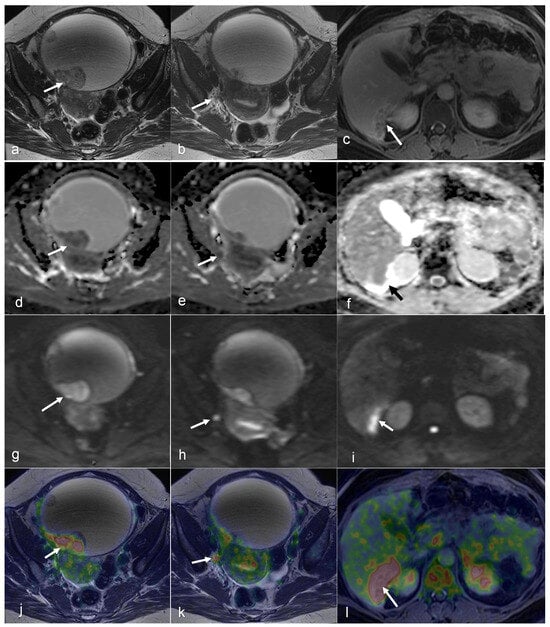

3.3. Ovarian Cancer

- Tsuyoshi, H.; Tsujikawa, T.; Yamada, S.; Okazawa, H.; Yoshida, Y. Diagnostic value of 18F-FDG PET/MRI for staging in patients with endometrial cancer. Cancer Imaging 2020, 20, 75. [Google Scholar] [CrossRef]

- Kitajima, K.; Suenaga, Y.; Ueno, Y.; Kanda, T.; Maeda, T.; Takahashi, S.; Ebina, Y.; Miyahara, Y.; Yamada, H.; Sugimura, K. Value of fusion of PET and MRI for staging of endometrial cancer: Comparison with ¹⁸F-FDG contrast-enhanced PET/CT and dynamic contrast-enhanced pelvic MRI. Eur. J. Radiol. 2013, 82, 1672–1676. [Google Scholar] [CrossRef]

- Ironi, G.; Mapelli, P.; Bergamini, A.; Fallanca, F.; Candotti, G.; Gnasso, C.; Taccagni, G.L.; Sant’Angelo, M.; Scifo, P.; Bezzi, C.; et al. Hybrid PET/MRI in Staging Endometrial Cancer: Diagnostic and Predictive Value in a Prospective Cohort. Clin. Nucl. Med. 2022, 47, e221–e229. [Google Scholar] [CrossRef]

- Fiaschetti, V.; Calabria, F.; Crusco, S.; Meschini, A.; Nucera, F.; Schillaci, O.; Simonetti, G. MR-PET fusion imaging in evaluating adnexal lesions: A preliminary study. Radiol. Med. 2011, 116, 1288–1302. [Google Scholar] [CrossRef] [PubMed]